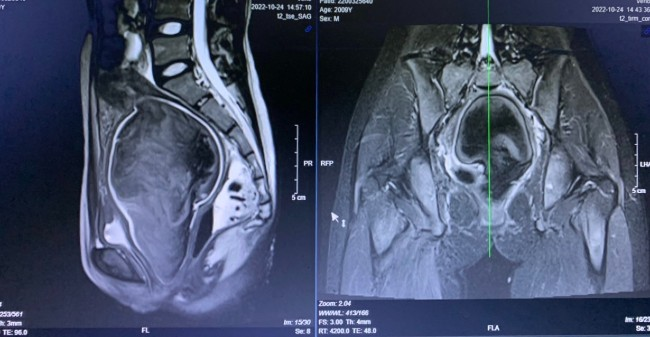

Tổn thương trên phim MRI bụng bệnh nhân. Ảnh: BVĐK tỉnh cung cấp.

Sau thăm khám, làm các xét nghiệm, các bác sĩ trong kíp trực nhận định đây là một trường hợp dị dạng tử cung đôi có tắc nghẽn âm đạo. Sáng 25.10, bệnh nhân được phẫu thuật xẻ túi cùng âm đạo thoát khối máu tụ trong lòng tử cung bế tắc.

Theo TS.BS Lê Thanh Hùng, đây là trường hợp dị dạng hiếm gặp. Nếu không chẩn đoán đúng và phẫu thuật kịp thời, khối máu (hành kinh) tụ trong lòng tử cung bế tắc sẽ vỡ gây viêm phúc mạc, nguy hiểm đến tính mạng. Đồng thời, nếu không hiểu sâu về phôi thai học và sinh lý bệnh để chẩn đoán đúng, có thể phẫu thuật nhầm với viêm phúc mạc ruột thừa hoặc nang buồng trứng xoắn, dẫn đến phải chuyển bệnh nhi lên tuyến cao hơn để phẫu thuật lại.